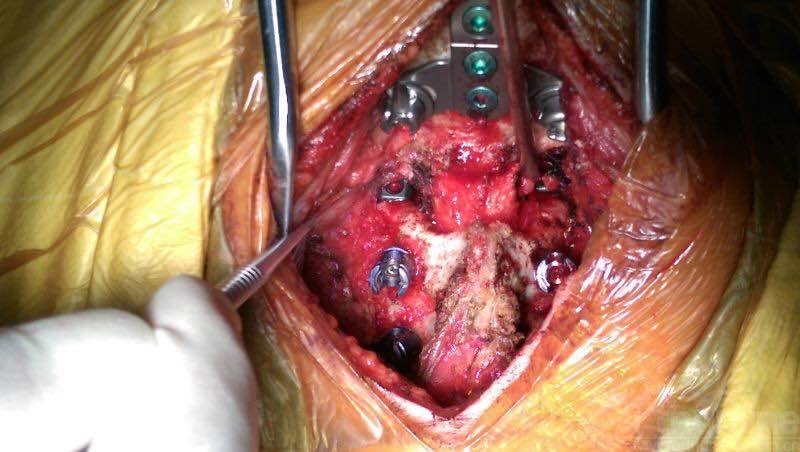

术中照片